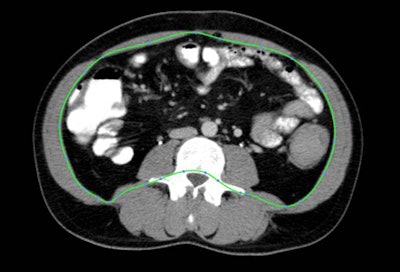

![]() |

| Fatty regions were isolated and measured based on attenuation of CT images at a single slice (L4/5 intervertebral disk + 6 cm). All images courtesy of Áine Ní Laoire and lead investigator Dr. Michael Maher, University of Cork, Ireland. |

All fat measurements were taken at a single CT slice location (L4/5 intervertebral disk + 6 cm), with investigators measuring visceral adipose tissue area (VAT area, cm2) and subcutaneous adipose tissue area (SAT area, cm2) based on tissue attenuation ranging from -150 to -50 HU. Body mass index was calculated from measurements taken at the L1 level, and CT images were examined using an open-source software package (OsiriX, Geneva), Laoire said. Fifty images were randomly selected for reliability testing using the Bland-Altman method and were found to be acceptable.